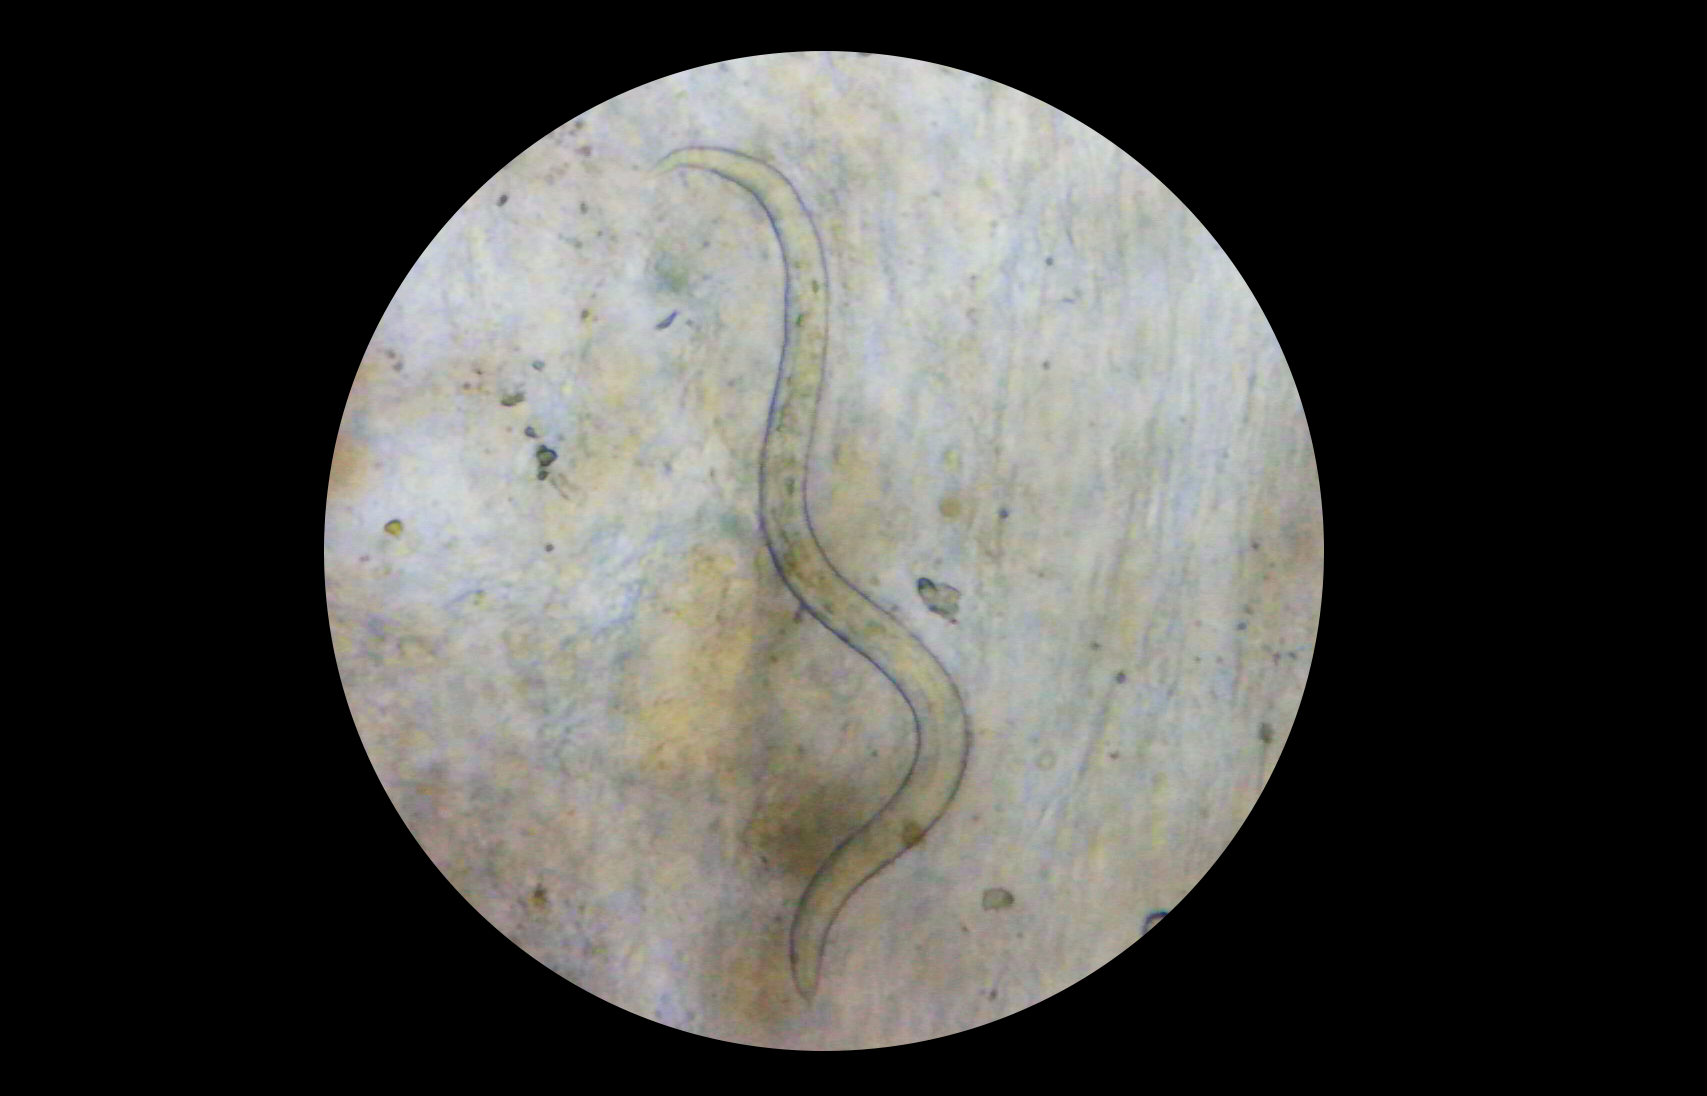

2. Vor einer Entwurmung sollte per Mikroskop eine Kotuntersuchung durchgeführt werden. Wir empfehlen Kotproben von insgesamt 3 Tagen zu untersuchen und ggf. später zu wiederholen.

3. Jeder Innenparasit (wie hier im Bild z.B. eine Lungenwurmlarve) muss gezielt mit dem passenden Medikament behandelt werden.

Eine pauschale Entwurmung gibt es nicht. Gerade wenn kranke Igel ins Warme geholt werden, explodieren meist die Innenparasiten. Daher ist hier Sorgfalt geboten!